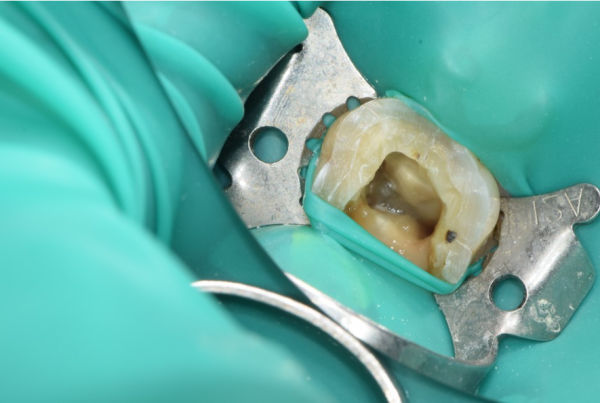

클램프로 러버댐을 고정하여 신경치료를 진행합니다.

Fix the rubber dam with a clamp to proceed with neurotherapy.

신경치료를 할때는 완벽한 방습환경을 만들어 치료중에

오염이 되지 않도록 하는것이 아주 중요하기 때문입니다.

만약 이 과정에서 오염물질이 들어가게되면 신경치료를 끝냈어도

다시 문제가 생길 수 있습니다.

When you do neurotherapy, you create a perfect moisture-proof environment.

Because it's very important not to be contaminated.

If any contaminants are found in this process, even if you're done with nerve therapy,

Problems may arise again.

저희 태평역치과 더서울치과에서는 그러한 문제가 생기지 않도록

완벽하게 방습환경을 만들어 놓고 이렇게 근관 속에 빈틈없이 수복재료가

들어갈 수 있도록 신경치료를 진행합니다.

Taepyeong Station Dental Clinic, The Seoul Dental Clinic, to prevent such problems,

It's a perfect moisture-proof environment, and the restorative ingredients in the root canal

Neurotherapy is performed so that you can enter.